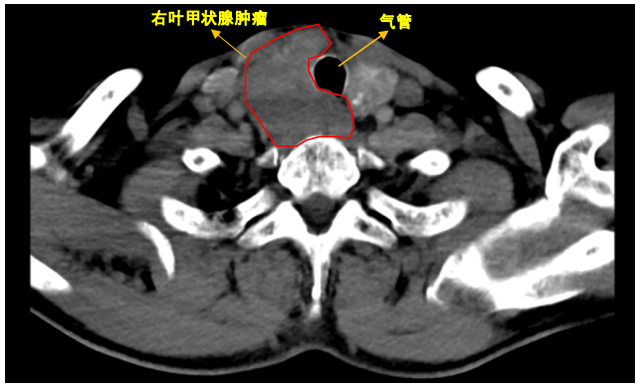

CT检查结果,令他直接吓瘫—— 甲状腺肿物把气管压变形 ,双肺还长出可疑结节!再经过B超和穿刺活检,确诊为甲状腺双叶乳头状癌+淋巴结转移 !

孙先生问:“是不是手术直接切掉就没事了?”甲乳外科医生摇头表示:“癌灶已经侵犯食管气管,只能先靠靶向治疗缩小肿瘤……”

当肿瘤增大压迫气管,会出现呼吸困难、气短;压迫食管,可导致吞咽困难;侵犯喉返神经,则会引起声音嘶哑。